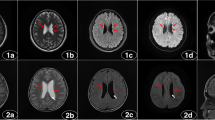

PET/CT reading and statistical analysis were used to classify CCD; 77 patients (77.0%) were classified as CCD− (mean age 24.0 ± 9.7 years), and 23 patients (23.0%) were classified as CCD+ (mean age 25.0 ± 7.5 years). In total, we found 220 hypometabolic regions by qualitative analysis of the interictal PET/CT images. The most common location of hypometabolic regions was the anterior temporal lobe (82/220, 37.3%) (Fig. 2), followed by the anterior frontal lobe (52/220, 23.6%), then successively parietal (31/220, 14.1%), posterior frontal (30/220, 13.6%), posterior temporal (16/220, 7.3%), and occipital (9/220, 4.1%).

Male, 27 years, age of onset 20 years, and duration of epilepsy 7 years. Interictal 18F-FDG PET/CT images show hypometabolism in the left anterior temporal lobe (ellipse; a axial, b coronal) and contralateral cerebellum (ellipse; c axial, d coronal) on PET images, without significant abnormalities on CT images (e–h). The pathology after surgery was FCD IIb in the left anterior temporal lobe

Female, 52 years, age of onset 6 years, and duration of epilepsy 46 years. Interictal 18F-FDG PET images before surgery show hypometabolism in the left anterior temporal lobe and contralateral cerebellum (red arrow), without significant abnormalities on MRI images. The pathology after surgery (anterior temporal lobe lesion resection) was FCD Ic in the left anterior temporal lobe. After 1 year of the surgery, interictal 18F-FDG PET images show metabolic defect of the surgery area (red arrow), hypometabolism in the left adjacent temporal lobe (white arrow), but the contralateral cerebellum show normal metabolism, the MRI just show postoperative changes (red arrow). Follow-up after 1 year of surgery is Engel class III

Male, 45 years, age of onset 15 years, and duration of epilepsy 30 years. Interictal 18F-FDG PET images before surgery show hypometabolism in the right anterior temporal lobe (red arrow), without significant abnormalities on MRI images. The pathology after surgery (anterior temporal lobe lesion resection) was FCD I in the right anterior temporal lobe. After 2 years of the surgery, interictal 18F-FDG PET images show metabolic defect of the surgery area (red arrow), hypometabolism in the right adjacent temporal lobe, right anterior front and contralateral cerebellum (white arrow), the MRI just show postoperative changes(red arrow). Follow-up after 2 years of surgery is Engel class IV